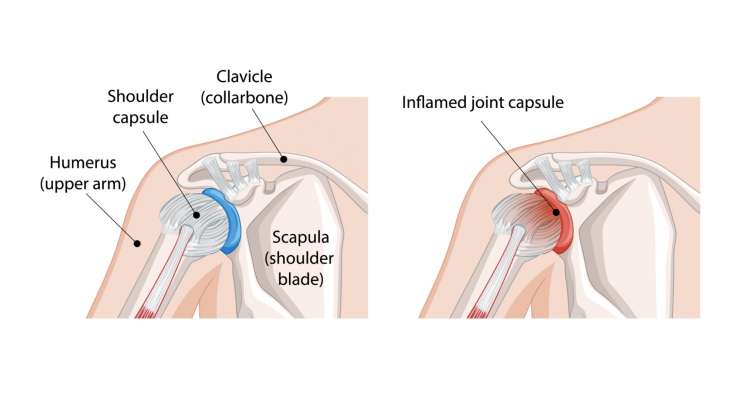

Замороженное плечо

Замороженное плечо — это болезненная тугоподвижность плеча, которую профессор, доктор медицины Франк Мартетшлегер сначала лечит консервативными методами с помощью физиотерапии и инъекций, а в запущенных случаях — артроскопически, чтобы восстановить подвижность сустава.